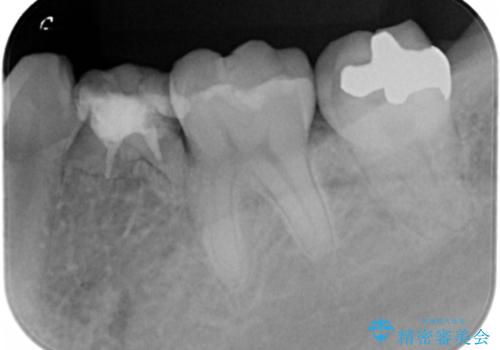

- 大人になっても残存していた乳歯がグラグラし、痛くて噛めない 抜いて欲しいとの希望で来院されました。

歯根が吸収し残すことのできない乳歯を抜去後、隣の歯を削らずに済むインプラント治療で咬合機能の回復を計画します。

乳歯の抜去後、インプラントを用いてしっかりと咬合機能を回復することができました。